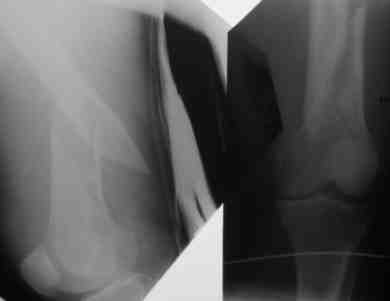

Не понял, почему это совершенно штатное использование этого гвоздя отнесено к "гаражной ортопедии"? Этот гвоздь задуман как универсальный, пригодный для около- и внутрисуставных ппереломов, и для и анте-, и ретроградного введения.

ВБ> Есть сомнения в жесткости конструкции!

В этом гвозде со стороны кондуктора можно ввести 3 статических винта (2 в круглые отверстия и одно по краю овального). Профиль не очень четкий, непонятно, есть ли вообще винты сквозь отверстия в гвозде? Если нет, то этих блокирующих (poller) винтов мимо гвоздя у вас столько, что канал сужен уже достаточно для устойчивого положения.

Он выпускается уже года 2, от UFN отличается дополнительым статическим отверстием на проксимальном конце, и возможностью ввести 4 винта: в 2 статических отверстия и по обоим краям овального.

На дистальном конце 2 статических отверстия, одно из них - передне-заднее, и овальное отверстие максимально дистально, в него можно ввести либо статический, либо динамический винты. Если ввести сразу 3 винта - они заклиниваются, создавая угловую стабильность.

Отверстия расположены более кучно. То есть гвоздь можно использовать не только при диафизарных, но и метафизарных переломах. Можно вводить и анте-, и ретроградно. При ретроградном варианте вверху запирать гвоздь удобнее через передне-заднее отверстие. Картинки в приложении.